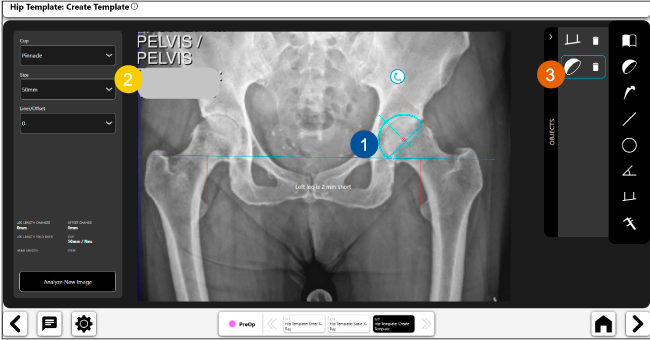

Planeación preoperatoria mediante la creación de plantillas digitales para reemplazo de cadera y análisis intraoperatorio

Disponibilidad de plantillas digitales de cadera.

Expediente histórico y personalizado, optimiza la planeación con el calendario de casos realizados en Velys TM y utiliza los íconos interactivos para una rápida revisión.

Mayor nivel de información intraoperatoria facilita la colocación correcta de los implantes:

Anotaciones digitales y herramientas de análisis de longitud de pierna.